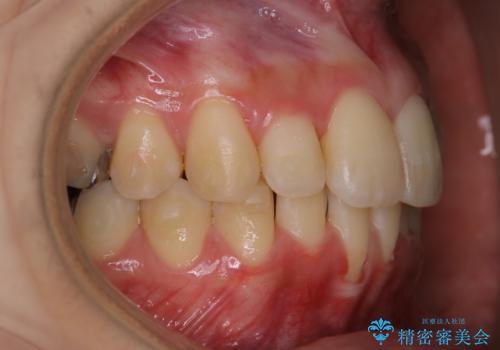

- 現在インビザラインでの矯正中で、歯の汚れが気になってきたためクリーニング希望とのことでした。PMTC60分コースを行いました。

毎日丁寧に歯磨きをしていても、日常生活での飲食物などにより着色してしまうことはあります。

PMTC(保険外治療)は、毎日の歯磨きで落としきれない汚れや、コーヒ、紅茶・タバコのヤニなどの着色も除去します。目には見えない歯と歯の間・歯肉の境目・インビザライン中はアタッチメント周囲などに残っているプラーク(歯垢)もしっかり取り除きます。PMTCでは専門的な機械や材料を使用して、徹底的に汚れを除去するため、虫歯・歯周病・口臭予防などにつながります。